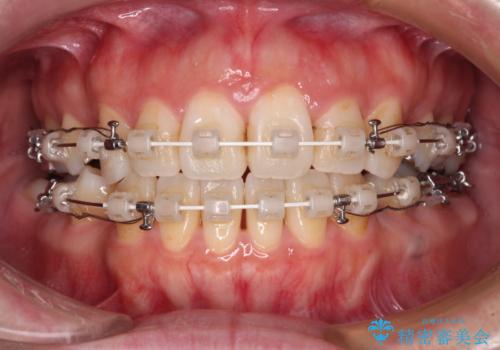

出っ歯と奥歯の欠損 ワイヤー矯正とインプラント治療

- 口元の突出感と奥歯の欠損を気にして来院された患者様です。

口元の突出感改善には、上下左右の第一小臼歯4本を抜歯し、奥歯の欠損部には矯正治療の途中でインプランを埋入していくこととしました。

矯正治療の後半にインプラント埋入を行うことで、トータルの治療期間を短縮することができました。